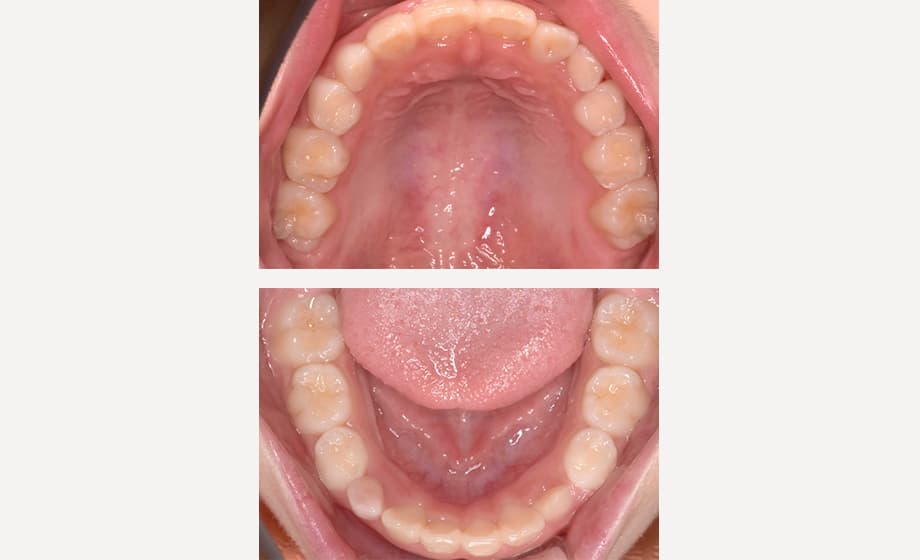

小児矯正では、お子さんの年齢や歯が生える状態によって乳歯列期、混合歯列期(Ⅰ期治療)、永久歯列期(Ⅱ期治療)に分けられます。

小児矯正では、あごの成長力を活かして歯の並ぶスペースを広げるように治療を進めます。そのため、スペース不足を補うための抜歯をしなくても済む可能性が高くなります。

小児矯正では、あごを広げる治療やお口まわりのクセの改善を通じて、歯並びが乱れる根本的な原因にアプローチします。そのため、治療後に歯並びが後戻りしにくいという特徴があります。

12~13歳頃に永久歯が生えそろうタイミングで、歯並びや噛み合わせがきれいに整っているかを診査し、必要に応じてⅡ期治療をご提案いたします。